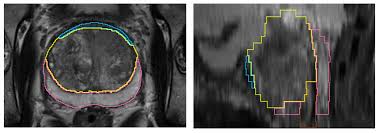

Revisiting Quantitative Multi Parametric Mri Of Benign Prostatic Hyperplasia And Its Differentiation From Transition Zone Cancer Springerlink

Revisiting Quantitative Multi Parametric Mri Of Benign Prostatic Hyperplasia And Its Differentiation From Transition Zone Cancer Springerlink from media.springernature.com